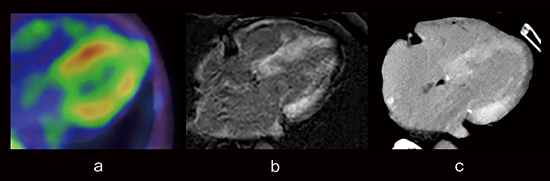

図5の症例は,心アミロイドーシスである。ピロリン酸シンチグラフィ(図5 a),CMR-LGE(図5 b)においてびまん性に肥厚した心筋の線維化組織が明瞭に観察でき,IQonの遅延造影画像(図5 c)でも同様の画像所見を認める。

図5 心筋遅延造影画像:心アミロイドーシス

a:ピロリン酸シンチグラフィ b:CMR-LGE

c:IQon-MonoE 40keV遅延造影画像

(画像ご提供:熊本中央病院様)